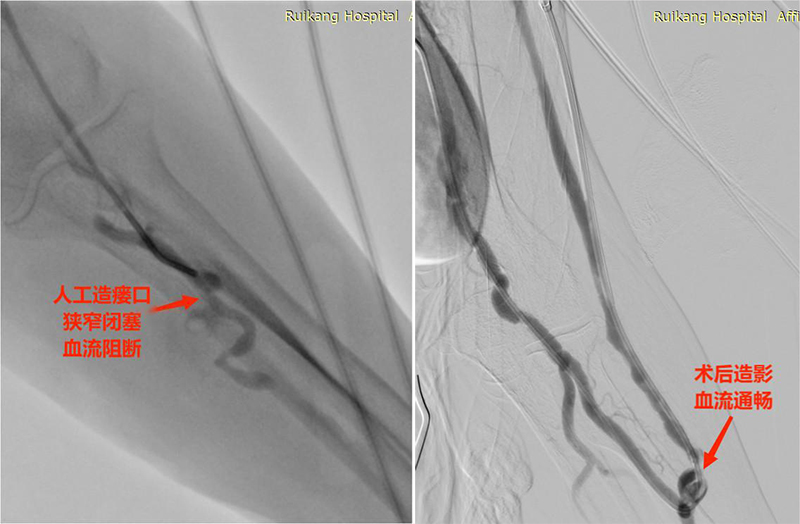

经过详细的术前准备并与其家属进行知情谈话后,胸心血管外科于10月30日为舒阿姨安排了介入手术。科室团队通过介入多种技术手段的融合,最终顺利为舒阿姨打通了左上肢人工造瘘口,并于中心静脉置入支架,成功为舒阿姨打通了一条位置更好的“生命线”。

术后舒阿姨恢复良好,左上肢瘘已经能够正常地进行血透,多年紧皱的眉头也得以慢慢舒展开来。

术前术后对比